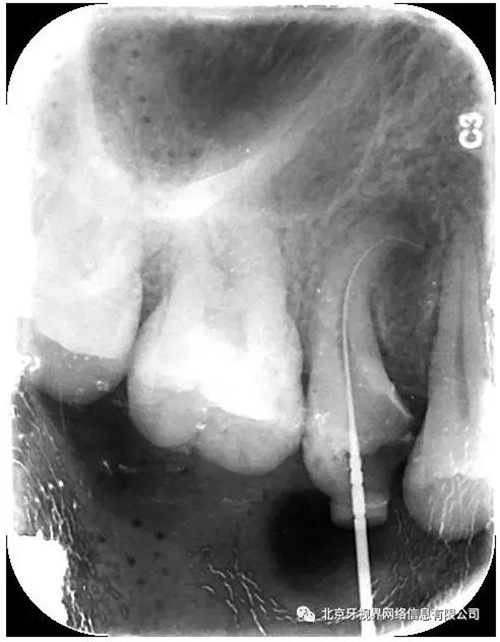

15備洞,揭頂,10#擴(kuò)大器預(yù)彎后疏通至全長(zhǎng),次氯酸鈉加超聲蕩洗,氫氧化鈣糊劑封藥,玻璃離子暫封,隨診。

2次復(fù)診常規(guī)根備加根充(AH-plus糊劑加牙膠尖根充)

4.此例病例中,術(shù)前分析后,采取先解放其中上段后,10#擴(kuò)大器預(yù)彎緩慢前行,抵達(dá)根尖區(qū)。

最后附帶近期彎曲根管的圖片